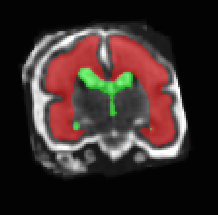

Limiting failures of machine learning systems is of paramount importance for safety-critical applications. In order to improve the robustness of machine learning systems, Distributionally Robust Optimization (DRO) has been proposed as a generalization of Empirical Risk Minimization (ERM). However, its use in deep learning has been severely restricted due to the relative inefficiency of the optimizers available for DRO in comparison to the wide-spread variants of Stochastic Gradient Descent (SGD) optimizers for ERM. We propose SGD with hardness weighted sampling, a principled and efficient optimization method for DRO in machine learning that is particularly suited in the context of deep learning. Similar to a hard example mining strategy in practice, the proposed algorithm is straightforward to implement and computationally as efficient as SGD-based optimizers used for deep learning, requiring minimal overhead computation. In contrast to typical ad hoc hard mining approaches, we prove the convergence of our DRO algorithm for over-parameterized deep learning networks with ReLU activation and a finite number of layers and parameters. Our experiments on fetal brain 3D MRI segmentation and brain tumor segmentation in MRI demonstrate the feasibility and the usefulness of our approach. Using our hardness weighted sampling for training a state-of-the-art deep learning pipeline leads to improved robustness to anatomical variabilities in automatic fetal brain 3D MRI segmentation using deep learning and to improved robustness to the image protocol variations in brain tumor segmentation. Our code is available at https://github.com/LucasFidon/HardnessWeightedSampler.